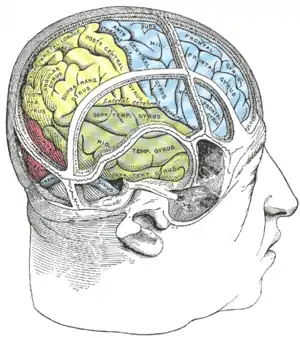

Lateral surface of left cerebral hemisphere, viewed from above. Drawing of a cast to illustrate the relations of the brain to the skull. (Supramarginal gyrus labeled at upper left, in yellow section.)

Drawing of a cast to illustrate the relations of the brain to the skull. (Supramarginal gyrus labeled at upper left, in yellow section.)